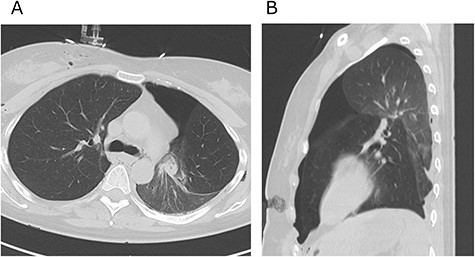

A 38-year-old woman with schizophrenia committed suicide by a self-infliction of sharp force into the chest and abdomen. She presented to our hospital in a critical condition. On arrival in the emergency room (ER), she developed hemorrhagic shock, which leads to an emergent abdominal damage control surgery under general anesthesia. She lost cardiac activity in the operating room during exploratory laparotomy. A left-sided basal thoracostomy, cross-clamping of the descending thoracic aorta, and open cardiac massage were also performed. She received gauze packing at the bleeding point and temporarily close the abdomen and chest wall. After the surgery, she was transferred to the intensive care unit with mechanical ventilation and recovered from hemorrhagic shock. Two days later, a second-look laparotomy was performed. ER doctors verified the hemostasis and closed the patient’s abdomen and chest. On the same day, a chest radiograph revealed pulmonary atelectasis of the left upper lobe (Fig. 1). Computed tomography (CT) revealed alveolar bleeding, pneumonia and atelectasis of the left upper lobe (Fig. 2). Despite antibiotic therapy and repeated endobronchial sputum aspiration, radiologic findings were not improved. On the seventh postoperative day, she was referred to our department for suspected lung abscess. When compared to the chest CT images on the day of initial surgery, pulmonary torsion was suggested (Fig. 3A). The sagittal CT images were reconstructed, and the torsion of the left upper lung lobe was diagnosed (Fig. 3B). Therefore, an emergency left upper lobectomy was performed through a left thoracotomy. Intraoperatively, the left upper lung lobe was rotated clockwise and was hemorrhagically and congestive infarcted. Due to severe pulmonary congestion, it was difficult to obtain the surgical field of view. The pericardial sac was opened and the intrapericardial isolation of the left upper pulmonary vein was performed. To prevent separation of the thrombus and necrotic material in the left upper lobe, we first dissected the left upper pulmonary vein before resolving the torsion and performing the lobectomy. She had a complete pulmonary fissure. Moreover, only one first pulmonary artery branch had ruled the approximately pulmonary arterial flow of her left upper lobe. The left upper lobectomy was performed. The patient made an uneventful recovery.

Axial (A) and sagittal (B) computed tomography images few hours after initial emergency operation.